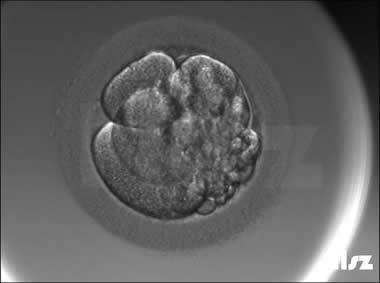

| |

| 卵裂球碎裂:受精卵第一次卵裂为2个细胞,但在2细胞阶段时,2个细胞均同时发生了碎裂。 | |